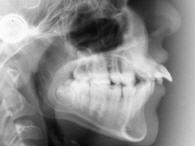

| Fernröntgenbild | Orthopantomogramm |